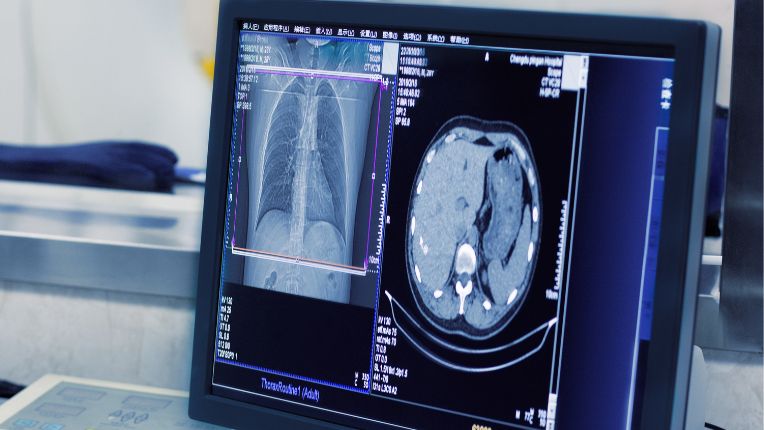

Radiographie et scanner sont deux techniques de radiologie utilisant les rayons X. La première est plus ancienne mais toujours aussi utile. La seconde est plus récente et offre des images en 3D.

Photo d'un scan

Photo d'une radiographie des poumons

Parmi ces techniques, l'on trouve la radiologie, technique la plus ancienne qui fait appel à des rayons X qui traversent le corps afin de produire une image en 2D de la zone du corps que l'on souhaite visualiser. Le scanner, technique plus récente, utilise aussi les rayons X mais propose des images en 3D. Pour passer un scanner on doit entrer dans une machine en forme d'anneau.

Le scanner, aussi appelé tomodensitométrie, est un appareil de radiologie qui offre la possibilité de voir le corps en deux ou trois dimensions. Les images qu'il propose sont très précises. Il utilise des rayons X. Le scanner se constitue d'un anneau ou d'un grand tube dans lequel le ou la patiente prend place. L'intérêt de cet appareil est de produire des coupes fines de la zone inspectée. Un produit de constraste peut être parfois nécessaire (il s'agit souvent d'un produit iodé).

La radiographie est une technique d'imagerie médicale, plus ancienne, mais qui reste souvent utilisée. Elle s'appuie aussi sur les rayons X et permet d'obtenir des images. C'est typiquement la technique utilisée par les dentistes pour visualiser la mâchoire. Un produit de contraste peut aussi être utilisé.